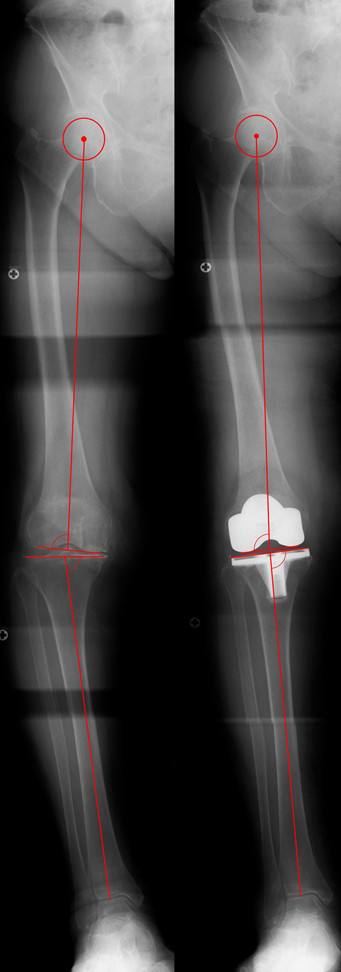

図 1: TKA 前後のレントゲン画像で、術前は O 脚、術後は真っ直ぐに変化している。本例では TKA への違和感があった。

図 2: TKA 前後のレントゲン画像で、術前は O 脚、術後も O 脚を維持している。本例では TKA への違和感がなく、機能も良好であった。